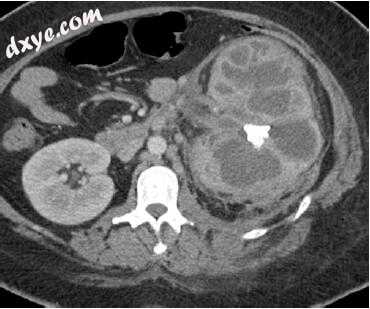

20.1.5急性肾/肾周脓肿

未经治疗或治疗不当的肾盂肾炎可导致化脓,液化和实质坏死,最终导致脓肿。具有脓肿形成风险的患者包括患有糖尿病,慢性疾病,免疫受损状态,尿路梗阻和静脉内药物滥用者的患者。肾脓肿往往是孤立的,可以减压进入肾周围空间或收集系统。在美国,它们通常是低回声的,通过传播,移动碎片,偶尔的气穴和彩色多普勒缺乏内部流动。US在确定围绕CT的肾周围延伸的存在和程度方面不太敏感;然而,这是一种适当的后续成像方式,可以寻找对治疗的反应,并作为经皮引流的指导。 CT展示了一种带有增强边缘的流体收集,其可能含有气体。大脓肿通常需要导管或手术引流(图20.1)。感染扩展到肾周围空间是常见的,并且可能发生肾周脓肿。额外的实质收集可以扩展到腰肌,骨盆或腹股沟。

1.jpg

图20.1一名患有艾滋病和发烧的37岁女性的肾脓肿。左肾的轴向对比增强CT图像显示复杂的外周增强液体收集和相关的肾周围绞合。随后排出的液体生长金黄色葡萄球菌